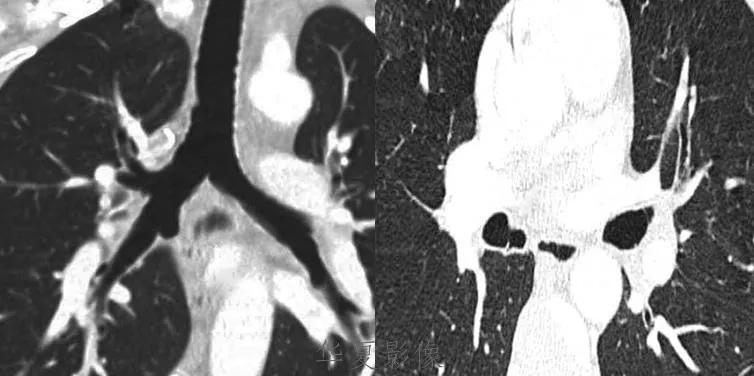

2.CT表现:前纵隔、中纵隔多组淋巴结肿大,常融合成块,尤其易累及血管前间隙组、主动脉弓旁、上腔静脉后组为最多见,易包绕上腔静脉等大血管及气管。肿块多呈均匀软组织密度,分叶状。轻到中度强化。放疗后肿块内易出现坏死、囊变、钙化灶。病人多伴有全身其他部位的淋巴结肿大。

3.MRI表现:肿大的淋巴结信号通常均匀,T1WI呈等或稍低信号,T2WI呈稍高信号。放疗后的纤维化在T2WI呈低信号,残余活动性肿瘤则为较高信号。